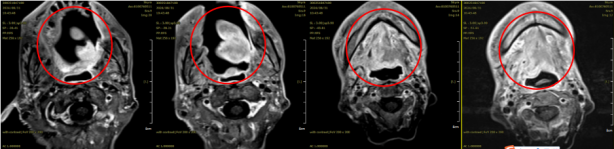

Figure 3: Post-treatment MRI: A mass in the tongue and right tongue base (4.1x2.1cm), showing a reduction in size compared to previous imaging. Clinical evaluation: PR (Partial Response).

In the case of the aforementioned tongue cancer patient, recent efficacy evaluation after carbon ion therapy showed partial remission, with significant symptom improvement, mild side effects, and good tolerance. This further confirms the effectiveness and safety of carbon ion radiotherapy in the treatment of tongue cancer.